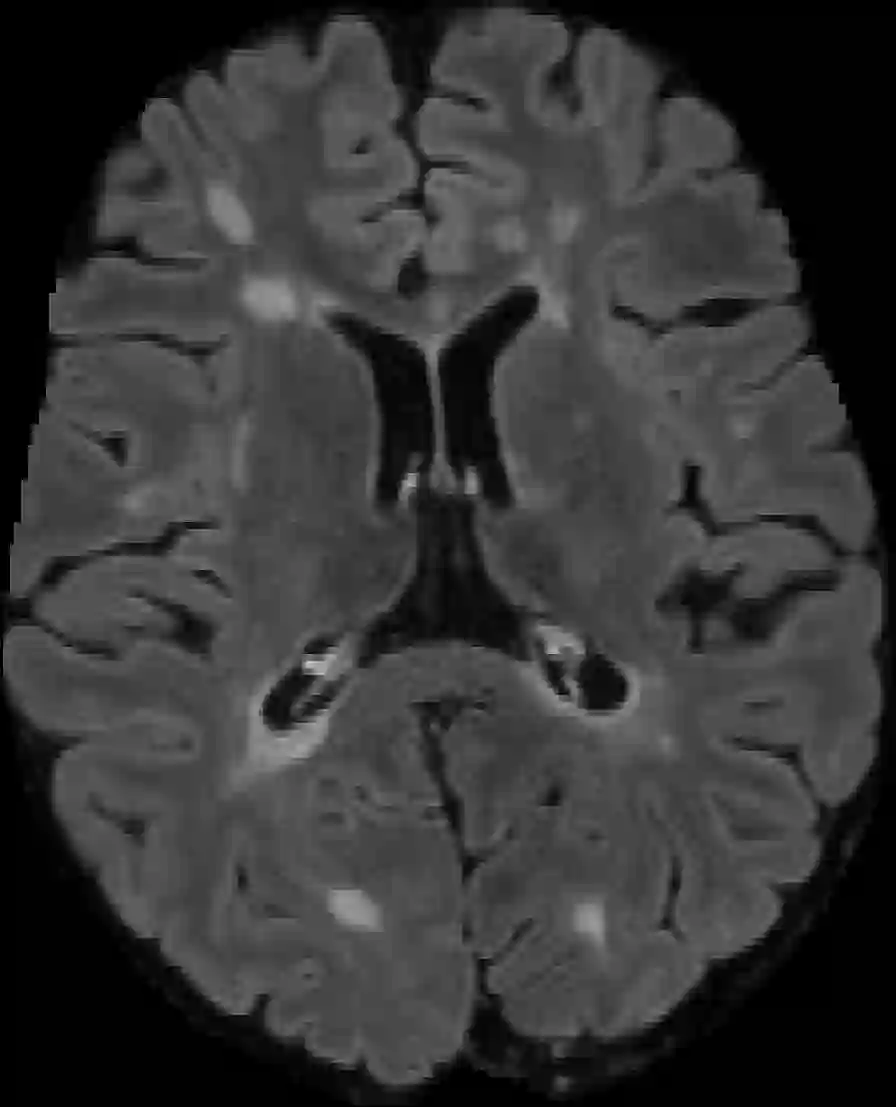

Assessment of lesions and their longitudinal progression from brain magnetic resonance (MR) images plays a crucial role in diagnosing and monitoring multiple sclerosis (MS). Machine learning models have demonstrated a great potential for automated MS lesion segmentation. Training such models typically requires large-scale high-quality datasets that are consistently annotated. However, MS imaging datasets are often small, segregated across multiple sites, with different formats (cross-sectional or longitudinal), and diverse annotation styles. This poses a significant challenge to train a unified MS lesion segmentation model. To tackle this challenge, we present SegHeD, a novel multi-dataset multi-task segmentation model that can incorporate heterogeneous data as input and perform all-lesion, new-lesion, as well as vanishing-lesion segmentation. Furthermore, we account for domain knowledge about MS lesions, incorporating longitudinal, spatial, and volumetric constraints into the segmentation model. SegHeD is assessed on five MS datasets and achieves a high performance in all, new, and vanishing-lesion segmentation, outperforming several state-of-the-art methods in this field.